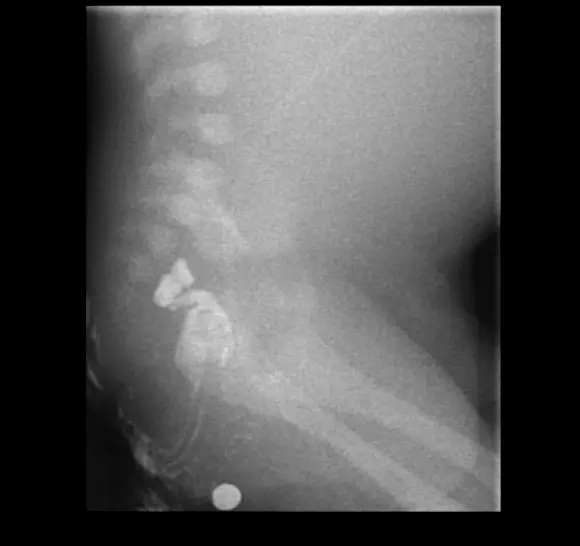

X-ray 촬영 : double-bubble sign

위장관 조영술

치료 : duodenoduodenostomy (십이지장 - 십이지장 문합술)을 통한 교정 수술